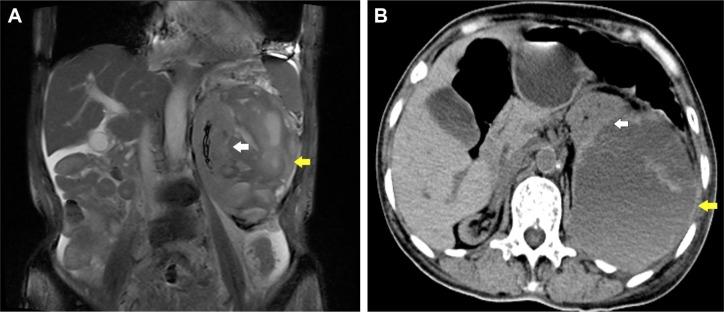

A 69-year-old male presented with pain in the left waist and back of 1 month duration. The renal abscess was suspected by magnetic resonance imaging before operation. The perirenal hematoma was cleaned by operation. In another case, the patient had a functional solitary left kidney compressed by a huge retroperitoneal mass and uropenia appeared.